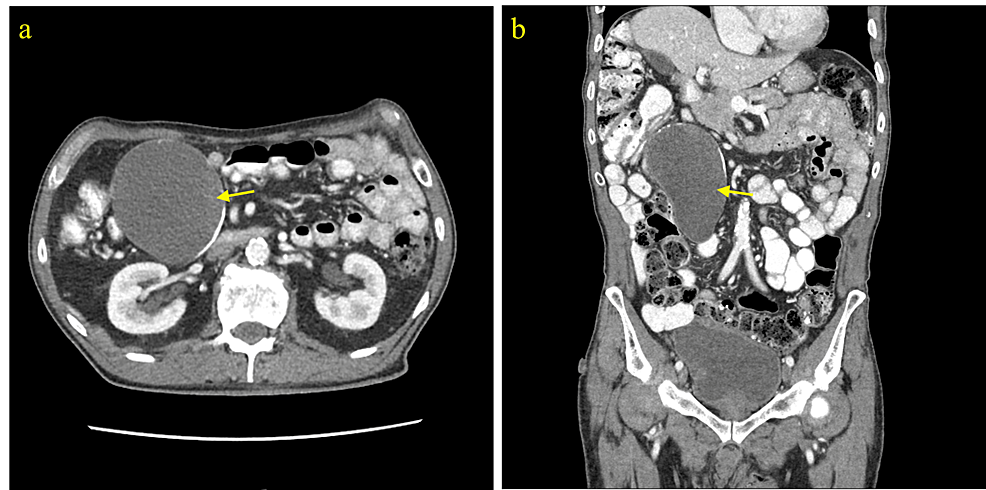

A 59-year-old male presented with microscopic hematuria. Renal ultrasound showed a large tubular lesion in the pelvis. CT abdomen and pelvis with IV and oral contrast demonstrated a 14.5 cm x 6.3 cm x 5.6 cm peripherally calcified tubular fluid attenuation lesion in the right hemipelvis. Though surgery was recommended for management, the patient declined surgery and wished to be managed non-operatively. The patient’s request was followed, and the patient was counseled that if the findings did not normalize on follow-up imaging after non-operative management, then surgery would be highly recommended. A follow-up CT scan with IV contrast five months later re-demonstrated the RLQ tubular cystic mass measuring 14.4 cm x 5.3 cm in the coronal plane with heterogeneous mural calcifications lying adjacent to the appendiceal tip. An open appendectomy was performed and the cystic appendiceal mass was removed (Figure 1). Because pathological examination demonstrated an LAMN confined to the appendix with an intact serosa and proximal and mesenteric bowel margins negative for neoplasms, staged as pTis, appendectomy alone was considered suitable for treatment.

Although LAMN can be generally asymptomatic and stable, it can also lead to a number of serious complications over time [1-3]. LAMN can rupture and disseminate mucin and neoplastic cells into the peritoneal cavity and result in PMP, an intraperitoneal accumulation of mucinous tumors and mucinous ascites that is associated with poor outcomes and high mortality risk [1-3]. Therefore, timely workup and management are essential to prevent progression to PMP and metastasis and improve overall outcome and recovery. Given it can be asymptomatic and have nonspecific findings when symptomatic, imaging is important for the initial detection of a mucinous appendix and surveillance for rupture. When intact, abdominal ultrasound can show a distended cystic appendix with porcelain wall calcification and a lamellated mucinous “onion-skin” appearance, though rupture will show an interruption in the appendiceal wall with leakage, while PMP will show thickening of the peritoneum or omentum, anechoic regions, echogenic foci, and septations [3]. CT can show an enlarged appendix with wall calcifications and thickening, and additionally demonstrate septations, calcified nodules, and liver margin scalloping in PMP (Figures 2–4) [1, 3]. Magnetic resonance imaging (MRI) can show a hyperintense distended appendix and bright mucin appearance on T2-weighted MRI, as well as nodularity on MRI with contrast [3]. A biopsy is not recommended due to perforation risk, though if the lesion has disseminated peritoneally, a biopsy of peritoneal nodules can be helpful for diagnosis [3]. Through these diagnostic measures, they can help to identify mucinous appendices, monitor for rupture, and allow for timely management to reduce the risk of dissemination and progression to PMP.